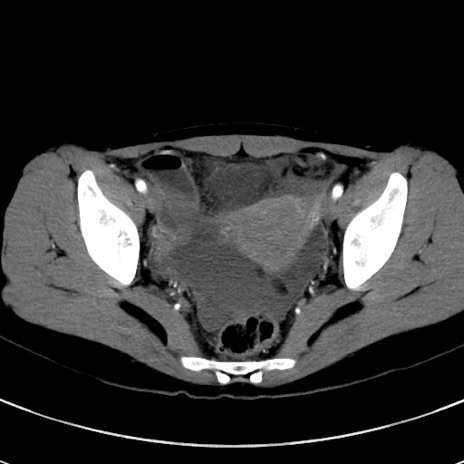

冠状断像

【症例】20歳代女性

【主訴】嘔吐、下腹部痛

【現病歴】昨日夕食後に嘔吐し下腹部痛が出現。本日になっても嘔吐持続し改善しないため来院。

【身体所見】意識清明、BT 37.2℃、BP 108/67mmHg、腹部:平坦、やや硬、下腹部正中から右にかけて圧痛あり、反跳痛軽度あり、tapping pain(+)。

【データ】WBC 13600、CRP 14.94